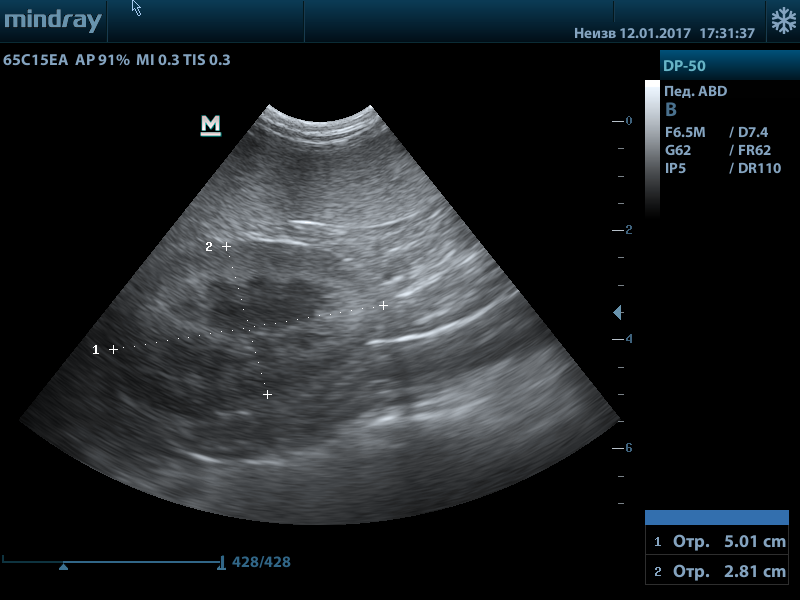

В норме размеры почек у взрослого человека имеют следующие размеры:

• длина почки 10–12 см,

• ширина до 6 см,

• толщина 4–5 см,

• толщина почечной ткани — паренхима 1,5–2,5 см.

Ультразвуковое изображение почек состоит из двух основных компонентов: изображений коркового слоя и синуса. Корковый слой почки выглядит гомогенным и нередко обладает меньшей эхоплотностью, чем печень. Синус почки содержит большие и малые чашечки крупные ветви почечных сосудов, а также жир, обусловленная своей эхогенностью.

Небольшие анэхогенные структуры округлой формы, часто видимые по краю коркового вещества почки, соответствуют неизмененным пирамидам медуллярного слоя.